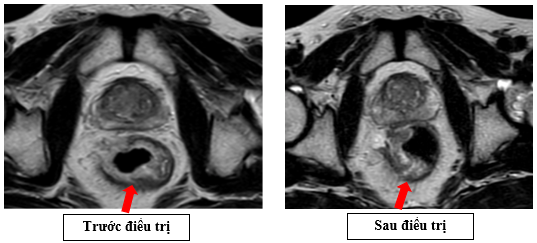

- Cộng hưởng từ vùng tiểu khung (09/2025): Hình ảnh dày không đều thành trực tràng đoạn cách lỗ hậu môn khoảng 3cm, dày lệch phải, dày nhất 11mm, dài khoảng 3mm, không rõ cấu trúc lớp, lớp thanh mạc còn đều, không thâm nhiễm xung quanh.

Hình 4: Bên trái (trước điều trị): khối u thành trực tràng dày, chiếm gần toàn bộ chu vi, lòng trực tràng hẹp rõ, tín hiệu xâm lấn ra ngoài lớp cơ. Bên phải (sau điều trị): khối u kích thước giảm, lòng trực tràng rộng hơn, tín hiệu khối u giảm, ranh giới với lớp mỡ quanh trực tràng rõ hơn -> khối u đáp ứng một phần